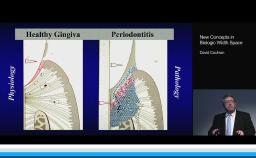

This lecture presents histomorphometric studies to demonstrate the strong relationship between bone and implant design, especially at the implant-abutment interface. The presenter shares key factors to explain the response of hard and soft tissue at the very first step of osseointegration. He focuses on the interaction between the design of the implant and the bone physiology. He develops the relationship between bone resorption and the inflammatory response of the host. The presenter also discusses different ways to decrease the inflammatory response at the implant-abutment interface. Supported by literature, a complete review of the various implant designs and their interactions with the bone is presented. The three major implant types are discussed: one-piece implant; two-piece implant with butt-joint interface; and two-piece implant with platform switching connection. This is a cutting edge lecture on the bone-implant relationship.